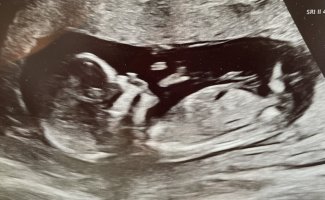

Holder en knapp på jente jegIkke her heller sikkert? Mente kanskje det under beina kanskje kunne være kjønnsorganet, men er sikker noe annet ja..

Spennende, får fasiten 14.mai forhåpentligvis på oulJeg tipper jente, uten å egentlig ha veldig peiling![]()

JenteIkke her heller sikkert? Mente kanskje det under beina kanskje kunne være kjønnsorganet, men er sikker noe annet ja..

Det kommer en liten jente til oss, så du hadde rett her! Det blir skikkelig stas etter 3 gutter!Ja, lov og si at det kanskje blir litt ekstra stas med jente da. Jeg synes den peker rett frem, så holder en knapp på jente. Du må oppdatere meg. Jeg har en gutt fra før, og håper jo litt på motsatt kjønn. Men legen trodde det var gutt hos oss igjen. Og det blir også veldig koselig med brødre![]()